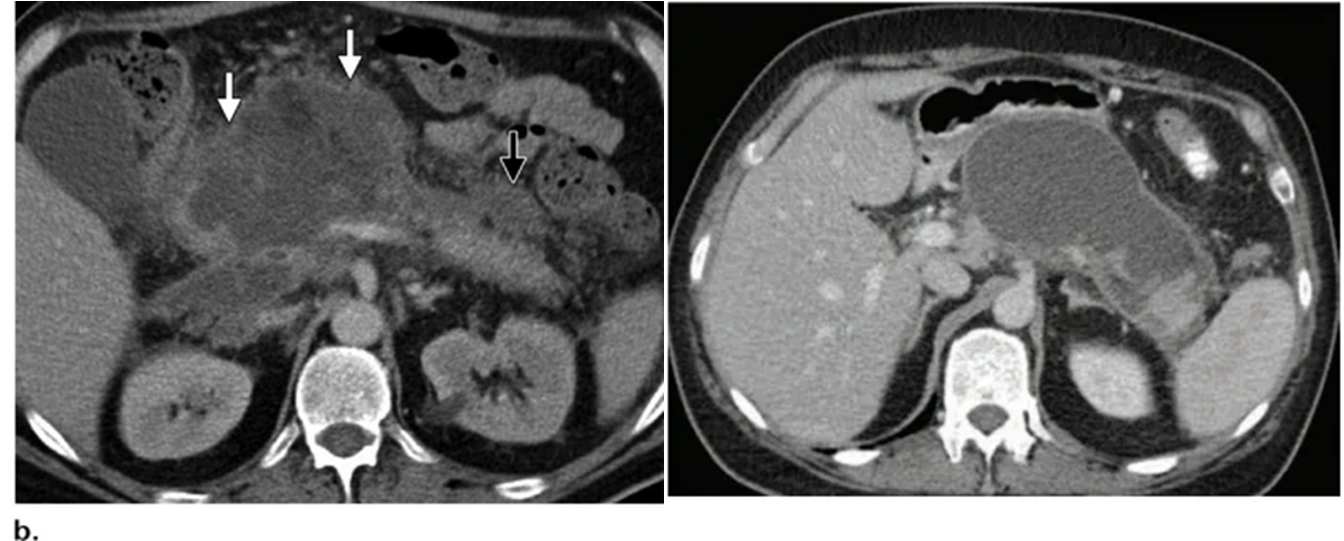

영상소견만으로 pseudocyst와 walled-off necrosis를 구분하는 것이 쉽지 않을 수 있다.

Pseudocyst는 췌장 효소로 구성되며, 정상 췌장 조직에 붙어있는 형태로 관찰된다. homogenous fluid를 보이며 비교적 regular 한 모양의 capsule을 갖는다.

WON의 경우 췌장조직과 주변 지방조직의 necrotic debris로 구성되어 heterogenous fluid를 보인다. WON은 괴사된 췌장 조직을 대체하여 형성되며 주변으로 remaining enhancing pancreas가 보이게 된다.